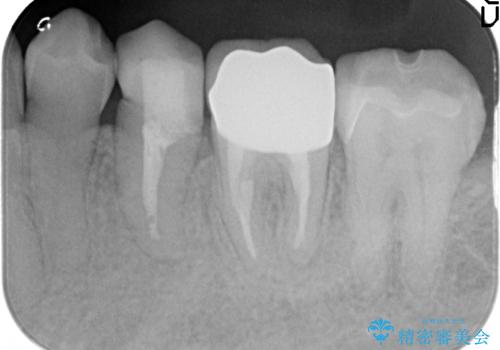

- 左下6番目の銀歯をオールセラミッククラウンにやり替えた症例です。

根管充填が不十分だったため再根管治療も行っております。

今回用いたオールセラミッククラウンはジルコニアフレームという白い素材の上にセラミックを盛っているため、審美性が非常に高いのが特徴です。

また、ジルコニアは人工ダイヤモンドの材料にも使われているほど高い強度を持っており、そのためオールセラミッククラウンは審美性だけでなく、奥歯やブリッジの補綴も可能とするクラウンです。